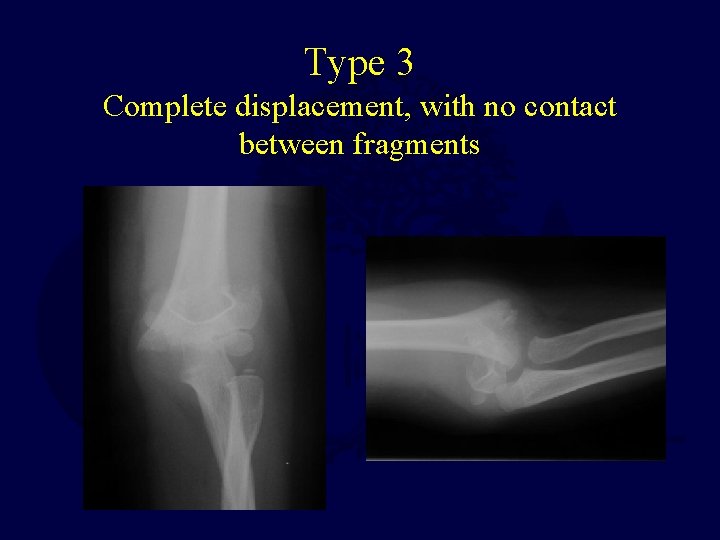

Supracondylar Humerus Fractures Classification • Type 1 – Non-displaced • Type 2 – Angulated/displaced fracture with intact posterior cortex • Type 3 – Complete displacement, with no contact between fragments Gartland. Management of supracondylar fractures of the humerus in children. Surg Gynecol Obstet. 1959; 109: 145 -54.

Type 3 Complete displacement, with no contact between fragments